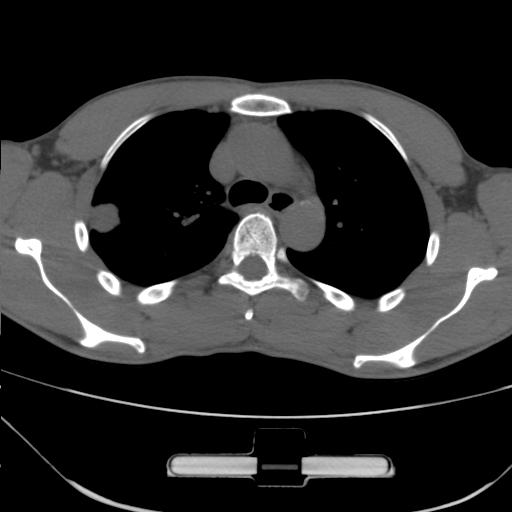

标题: CT25483:肺部病变 请指教

车祸伤者

右肺上叶后段近胸膜下结节样异常密度灶,似见分页及毛刺,考虑右肺上叶周围型肺ca,建议穿刺病理检查

缺乏病史,症状体征,但这个孤立结节具备了几乎所有的恶性征象:分叶,毛刺,空泡征,胸膜凹陷征,血管集束。